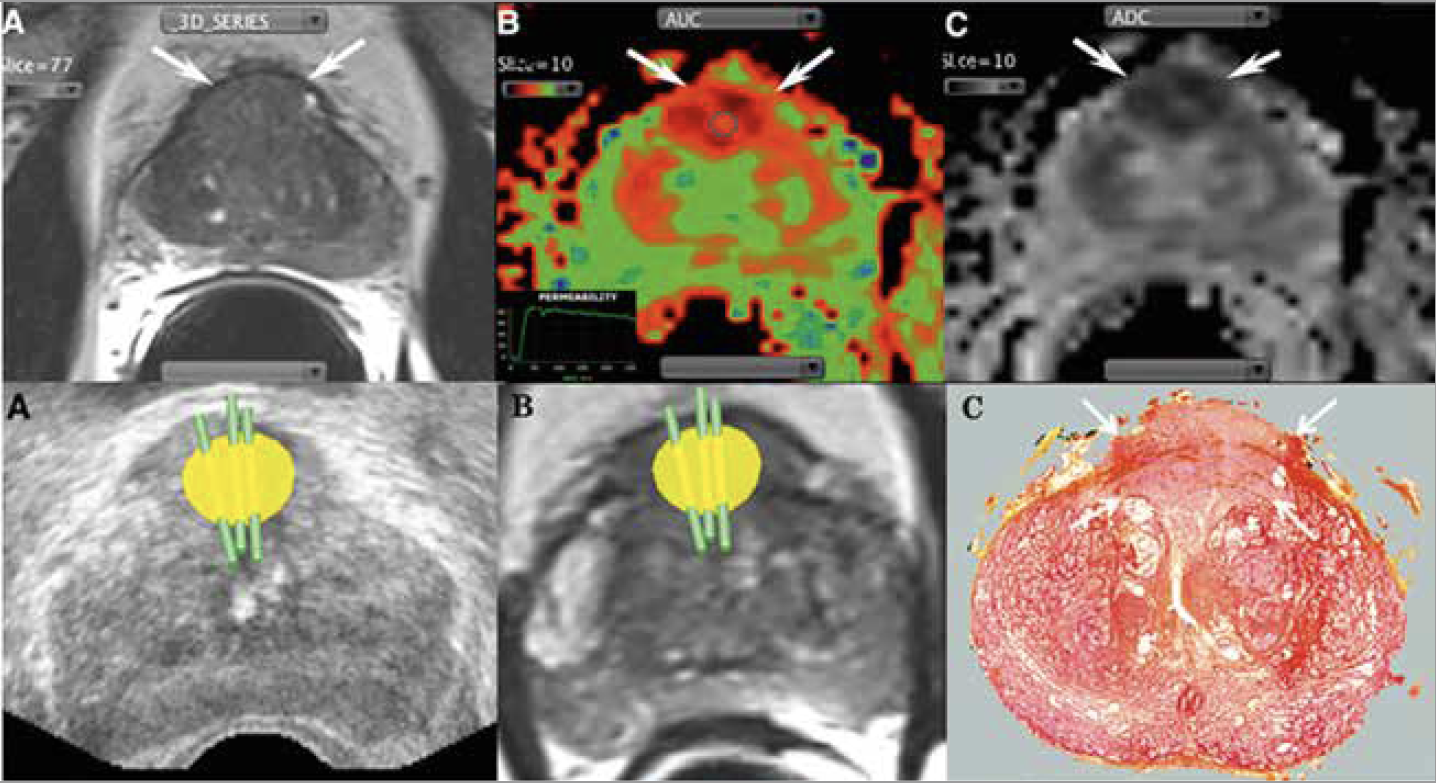

• La seconde méthode consiste à recaler les données d’IRM avec celles de l’échographie (fusion d’images) en utilisant un logiciel dédié (Fig. 4). Certains logiciels permettent même d’obtenir une reconstruction tridimensionnelle de la prostate avec une fusion d’images dite élastique qui recale les volumes IRM et échographiques en temps réel.

Figure 4 – Biopsies ciblées sous guidage échographique avec fusion d’images élastique IRM (24).

Patient de 69 ans avec un PSA à 9 ng/ml. Anomalie focale de la ZT antérieure médiane en

hyposignal T2 (A blanc, flèches), hypervascularisée (B blanc, flèches), avec baisse de l’ADC

(C blanc, flèches). Après fusion échographie-IRM 3D, trois biopsies sont réalisées au sein de la cible (A, B noirs) correspondant à un adénocarcinome (C noir, flèches) Gleason 7 : 4+3.

Cependant, des erreurs de ciblage sont toujours possibles, même chez des experts, notamment en raison des mouvements involontaires de la prostate et/ou du patient lors de la biopsie, et/ou à la non-concordance exacte des images lors du recalage.